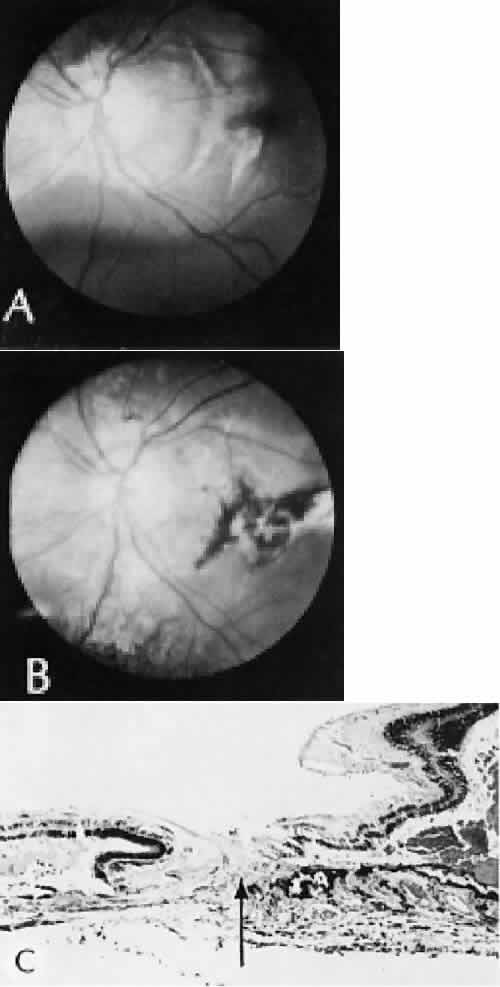

Wound healing of the neurosensory retina follows the principles of wound healing. There is an initial removal of all necrotic tissue by phagocytosis followed by proliferation of cells to form a chorioretinal bond. The healing, however, is modified in most instances by the lack of participation by the blood vessels.43–45 Astrocytes from the neurosensory retinaproliferate from the peripheral viable tissue into the wound and downward into the area of the subretinal space (Fig. 12). Retinal pigment epithelial cells from the peripheral viable tissue undergo fibrous metaplasia and proliferate upward into the area of the subretinal space. When the two proliferating cell types unite, a tight chorioretinal bond is formed. Increased retinal adhesiveness has been estimated to be 140% of the normal degree of adhesiveness 2 weeks after photocoagulation.46 Retinal holes may heal spontaneously if supported by an intact vitreous base or if located adjacent to the retinal pigment epithelium (Fig. 13).47,48 For the retinal pigment epithelium to differentiate, it must be in contact with overlying retinal pigment epithelium.49 Choriocapillaris repair from a photocoagulation wound of the retina appears to proceed in a manner similar to that of repair of capillary thrombosis in other tissues.50 The vascular repair process may not reproduce the lobular architecture of the native choriocapillaris.51 The choriocapillaris may regenerate in areas of restored retinal pigment epithelium.52 Proliferative vitreoretinopathy is an expression of abnormal retinal wound healing.53

Fig. 12. Light micrograph of an area over a retinal buckling element for retinal reattachment. Cryotherapy has been applied in the area, causing atrophy of the neurosensory elements of the retina. There is an intimate association of the remaining glial elements of the retina (R) with proliferated retinal pigment epithelial cells in the plane of the former subretinal space (arrow). The adhesion prevents intraretinal separation in this area. (Periodic acid-Schiff stain; × 100.)

Fig. 13. Retinal healing by proliferation of glial cells. In the presence of an intact vitreoretinal interface acting as a scaffolding, retinal glial cells are able to proliferate and seal small retinal holes. The arrow indicates artifactually detached vitreoretinal interface.